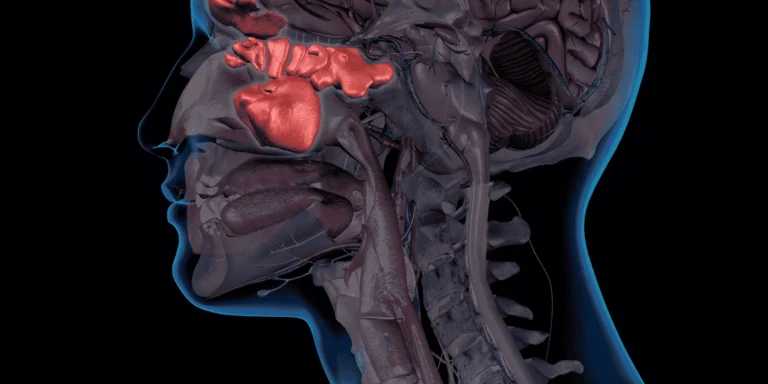

Acute bronchitis presents differently in adults and children, though there are common symptoms across age groups.

In adults, the hallmark symptom is a persistent cough that typically starts dry but often becomes productive with yellow or green mucus after a few days. This cough can last for 2-3 weeks, sometimes longer. Adults also commonly experience chest discomfort, mild fever, fatigue, shortness of breath, and wheezing, especially during physical activity.

Children with bronchitis may show similar symptoms, but with a few key differences. Their cough often sounds more “wet” or “junky” from the start. Children may become more irritable and tired than usual, and might show less interest in eating. Younger children and infants might have trouble breathing or feed more slowly due to nasal congestion.